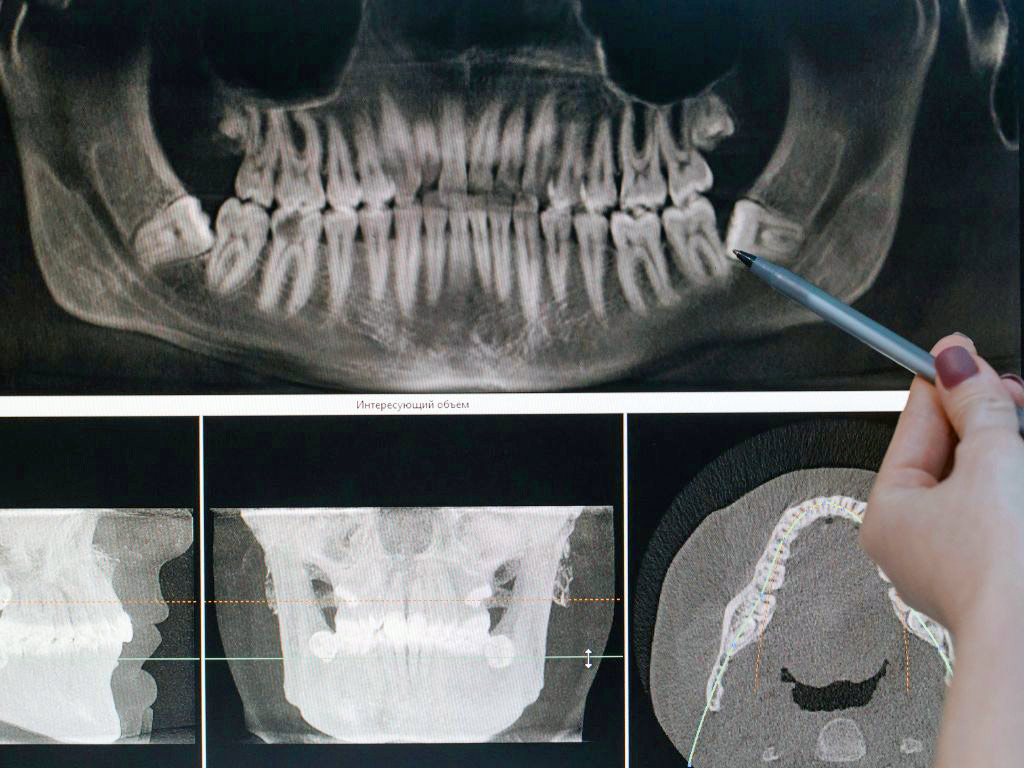

• Regularización ósea previa a rehabilitaciones o implantes.

Realizamos cada procedimiento con planificación detallada, tecnología de apoyo y técnicas mínimamente invasivas para reducir molestias postoperatorias. Además, te acompañamos antes, durante y después de la cirugía, entregándote indicaciones claras y seguimiento personalizado para que tu recuperación sea óptima.